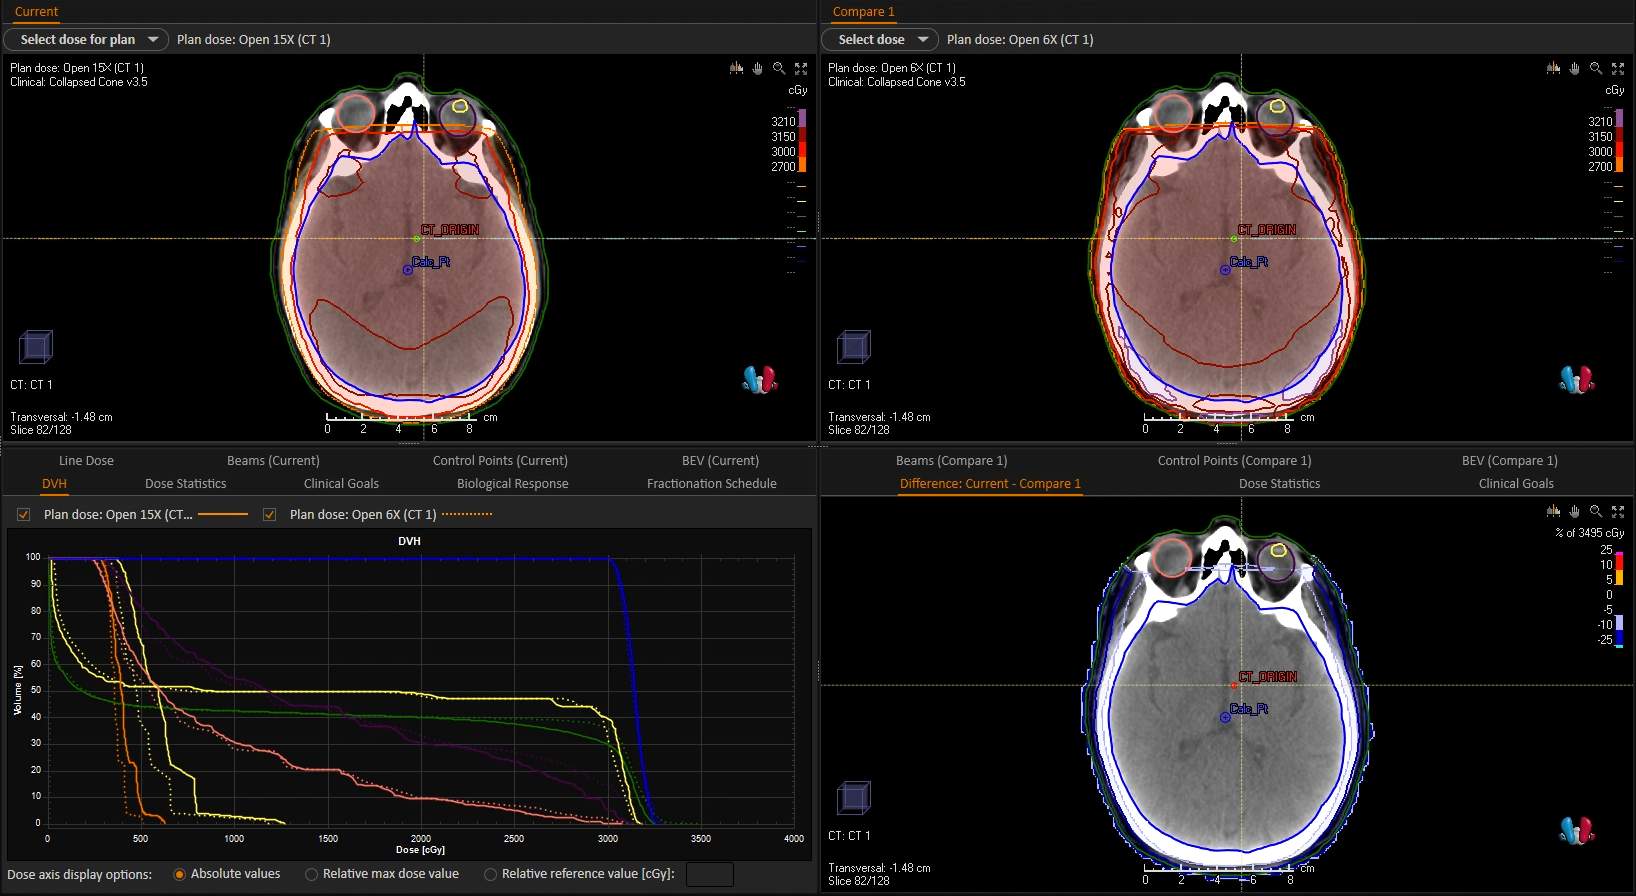

Lower energy (6x) photons are often used to cover the entire brain tissue. Higher energy (15x) photons are more penetrating; however, the skin-sparing effect can lead to underdosing of superficial brain tissue and the skull. The image shows a dose distribution comparison of the two energies.